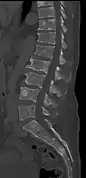

CT scan of the lower vertebral column in a man with multiple myeloma, showing multiple osteoblastic lesions: These are more radiodense (brighter in this image) than the surrounding cancellous bone, in contrast to osteolytic lesions, which are less radiodense.

The diagnostic examination of a person with suspected multiple myeloma typically includes a skeletal survey. This is a series of X-rays of the skull, axial skeleton, and proximal long bones. Myeloma activity sometimes appears as "lytic lesions" (with local disappearance of normal bone due to resorption) or as "punched-out lesions" on the skull X-ray ("raindrop skull"). Lesions may also be sclerotic, which is seen as radiodense.[70] Overall, the radiodensity of myeloma is between −30 and 120 Hounsfield units (HU).[71] Magnetic resonance imaging is more sensitive than simple X-rays in the detection of lytic lesions, and may supersede a skeletal survey, especially when vertebral disease is suspected. Occasionally, a CT scan is performed to measure the size of soft-tissue plasmacytomas. Nuclear Medicine Bone scans are typically not of any additional value in the workup of people with myeloma (no new bone formation; lytic lesions not well visualized on nuclear bone scan).